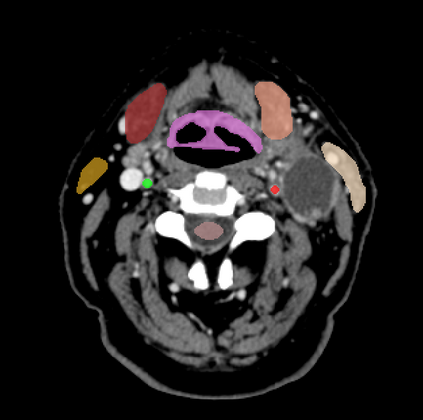

Organ at risk (OAR) segmentation is a critical process in radiotherapy treatment planning such as head and neck tumors. Nevertheless, in clinical practice, radiation oncologists predominantly perform OAR segmentations manually on CT scans. This manual process is highly time-consuming and expensive, limiting the number of patients who can receive timely radiotherapy. Additionally, CT scans offer lower soft-tissue contrast compared to MRI. Despite MRI providing superior soft-tissue visualization, its time-consuming nature makes it infeasible for real-time treatment planning. To address these challenges, we propose a method called SegReg, which utilizes Elastic Symmetric Normalization for registering MRI to perform OAR segmentation. SegReg outperforms the CT-only baseline by 16.78% in mDSC and 18.77% in mIoU, showing that it effectively combines the geometric accuracy of CT with the superior soft-tissue contrast of MRI, making accurate automated OAR segmentation for clinical practice become possible. See project website https://steve-zeyu-zhang.github.io/SegReg